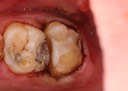

Joe Cha #19 pre-op

Joe Cha #18 pre-op